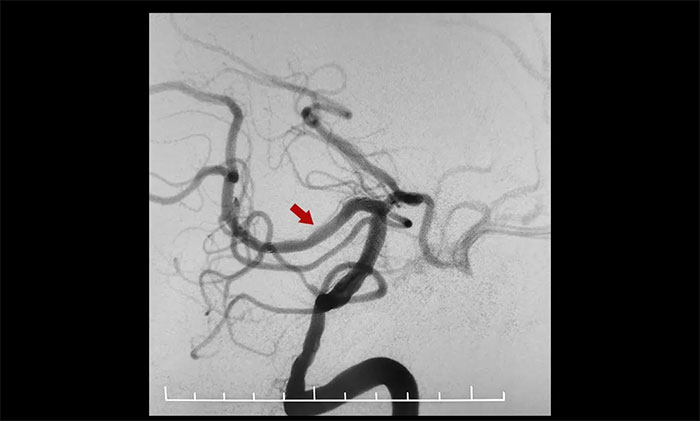

术中,通过输送型球囊扩张微导管轻松越过狭窄病变,完成右侧大脑后动脉狭窄段的球囊扩张及支架置入等步骤,无需进行微导管交换、球囊交换以及支架微导管交换的过程。手术治疗部分仅耗时30分钟。术后造影显示右侧大脑后动脉P1、P2交界段重度狭窄明显改善。行支架CT见支架成形良好。

▲ 术后,右侧大脑后动脉狭窄明显改善